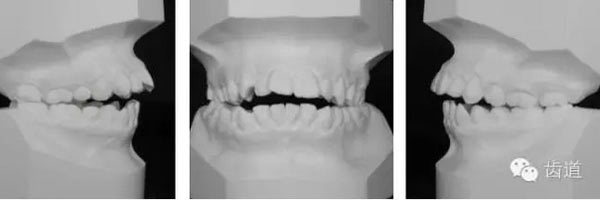

—面部左右不對(duì)稱

—頦部略右偏

—右頰部較豐滿

—唇肌較緊張,下唇略外翻

—均面形

![22].jpg 22].jpg](/UploadFiles/FCK/2015-12/6358465267254170152551924.jpg)

—凸面形

—鼻唇角略小,頦唇溝較淺

—下頜后縮,頦位靠后

—頦部形態(tài)不良、肌肉緊張

—上中線左偏,下中線右偏

—咬合平面右低左高

—前牙開(kāi)合

—右側(cè)磨牙近中關(guān)系,尖牙遠(yuǎn)中關(guān)系

—左側(cè)磨牙遠(yuǎn)中關(guān)系,尖牙近中關(guān)系

—前磨牙區(qū)及前牙區(qū)均為開(kāi)合

—右側(cè)自第一磨牙開(kāi)始至側(cè)切牙均為反合